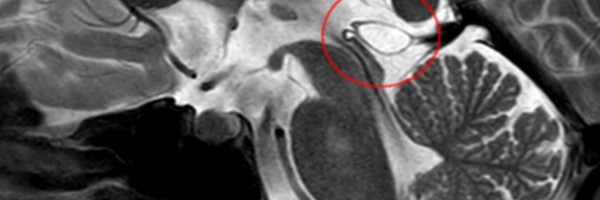

What Is A Pineal Cyst?

The pineal gland is a small, pine-shaped structure in the brain that produces melatonin, a hormone which helps regulate sleep patterns. This gland grow in size up to the age of two, after which the size stabilizes but increases in weight after puberty. Benign (non-cancerous) new growths in the